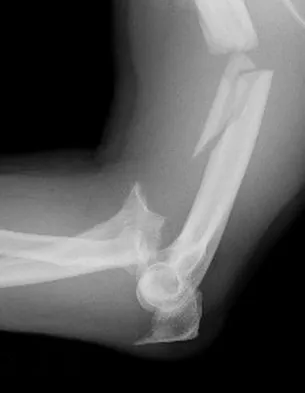

Question 218High Yield

A 32-year-old woman sustained an injury to her left upper extremity in a motor vehicle accident. Examination reveals a 2-cm wound in the mid portion of the dorsal surface of the upper arm and deformities at the elbow and forearm; there are no other injuries. Her vital signs are stable, and she has a base deficit of minus 1 and a lactate level of less than 2. Radiographs are shown in Figures 9a and 9b. In addition to urgent debridement of the humeral shaft fracture, management should include

Explanation

With a severe injury to the upper extremity, the best opportunity for achieving a good functional result for a floating elbow is immediate debridement of the open fracture, followed by internal fixation of the fractures. The ability to do this depends on the patient's physiologic status. In this patient, the procedure is acceptable because she has normal vital signs and no chest or abdominal injuries, and normal physiologic parameters (base excess and lactate) show adequate peripheral perfusion. The surgical approaches will be determined by the associated injury patterns and open wounds. In this patient, the humerus was debrided and stabilized through a posterior approach as was the medial condyle fracture. The ulna was fixed through an extension of the posterior incision and the radius through a separate dorsal approach. Solomon HB, Zadnik M, Eglseder WA: A review of outcomes in 18 patients with floating elbow. J Orthop Trauma 2003;17:563-570.